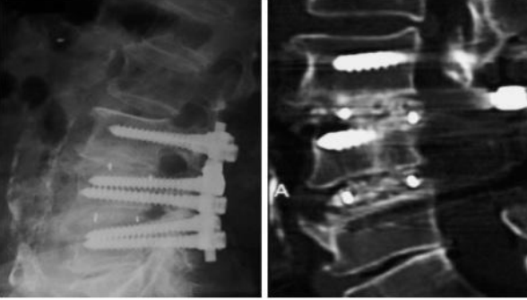

2.椎间远期融合效果好,沉降率低